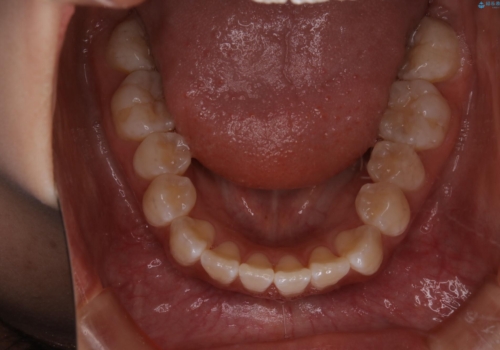

前歯のがたつきとオープンバイト:インビザラインでまとめて治す

- 噛み合わせと、前歯のがたつきが気になるとご相談にいらした方です。インビザラインFULLで綺麗な歯並びと噛み合わせを作ることが出来ました。

オープンバイトの方への治療は、通常抜歯を行いワイヤーによる矯正治療を行うことが多いですが、今回はインビザラインの特性を生かし、非抜歯にて綺麗な歯並びを作ることが出来ました。

舌癖がある方は、歯を内側から押し出す力が日常的に働くため、矯正治療後も歯と歯の隙間が開いてしまうなどの後戻りのリスクが高いことが知られています。舌の正しいポジショニングやお口周りの筋肉のトレーニングを行うことで後戻りのリスクを減らすことが可能です。